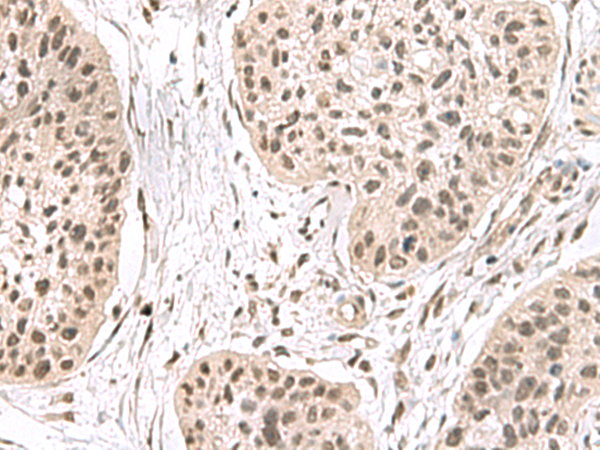

IHC positive control: |

Human esophagus cancer |

40-200 |